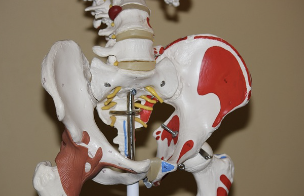

관절엔 콘드로이친 1200mg 콘드로이친 효능 및 부작용에 대해 알아보도록 하겠습니다. 콘드로이친은 연골 성장과 수분 보유에 필요한 성분으로, 관절의 쿠션 역할을 합니다. 연령이나 스트레스, 운동 부족 등으로 인해 연골이 손상되면 관절에 마찰과 염증이 발생하고, 통증과 강직감을 유발합니다. 콘드로이친은 연골의 재생을 도와주고, 관절의 윤활을 증가시켜줍니다. 콘드로이친은 보통 글루코사민과 함께 복용하는 경우가 많습니다. 글루코사민은 연골의 구조를 유지하고, 손상된 연골을 복구하는데 도움을 줍니다.

관절염은 연골이 손상되어 관절에 염증과 통증이 생기는 질환입니다. 콘드로이친은 연골 세포의 성장과 재생을 촉진하고, 연골을 분해하는 효소를 억제하여 관절염의 진행을 늦추고, 염증과 통증을 완화할 수 있습니다. 콘드로이친은 요통, 견통, 관절통, 근육통, 신경통 등 다양한 증상에 도움을 줍니다.

관절은 뼈와 뼈 사이에 있는 연골로 보호되고, 관절액으로 윤활되어 움직임이 부드럽고 유연합니다. 콘드로이친은 관절액의 점도를 높여주고, 수분 함량을 증가시켜 관절의 윤활작용을 강화합니다. 이는 관절의 마모와 충격을 방지하고, 움직임의 범위와 품질을 개선할 수 있습니다.